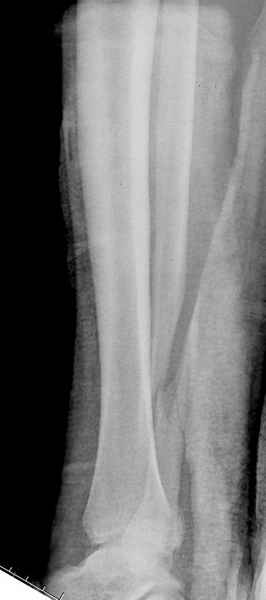

Конечно, компьютерный томограф более информативный метод, но с помощью недорогого обычного стандартного в нейтральном положении стопы: прямого, бокового и косой (ankle mortise) ренгенологического метода можно получить полную информацию о повреждении голеностопного сустава, а сравнительный снимок с другой стороны подтвердить наличие повреждения.

При реконструкции голеностопа, о важности восстановления длины малоберцовой для профилактики пост травматического артроза разбирали в предыдущих дискуссиях. Нарушенную биомеханику голеностопа без восстановления длины малоберцовой, не восстановить только швом медиальной связки.

Расширенная медиальная щель более чем на 4 мм и укорочение малоберцовой более чем 2 мм, а перелом заднего края большеберцовой смещения более 2мм с вовлечением 30% поверхности сустава, считается отходом от нормы голеностопного сустава, и подлежит к оперативному вмещательству.

Здесь похожий случай трехнедельной давности, перелом почти сросся и была укорочена малоберцовая, на операции длину малоберцовой смогли восстановить только после того, когда проксимальнее пластины ввели шуруп и использовали его как толкатель, с помощбю дистракционого инструмента (lamina spreader).

Меньше всего волнует положение медиальной лодыжки - в любое время можно провести остео или реостеосинтез, при несращении можно просто резецировать без ущерба для движений в голеностопе. Здесь обошлись фиксацией одним 4 мм канюлированным шурупом.